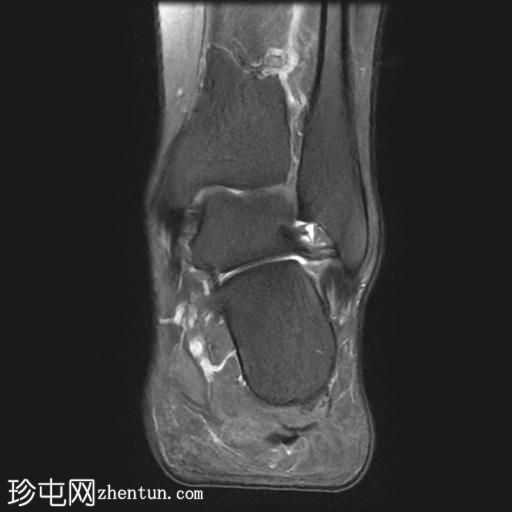

轴位

T2加权像

轴位PD加权像

足底筋膜附着处可见足底跟骨骨刺,伴有下方局灶性骨髓水肿。

足底筋膜跟骨起点处可见增厚,并伴有实质内液体信号增高,尤其是在中内侧纤维,提示足底筋膜炎。

足底筋膜炎是指足底筋膜的炎症,是足跟痛最常见的原因。该病常伴有足底筋膜附着于跟骨处的骨刺,这会加重症状的严重程度并延长病程。